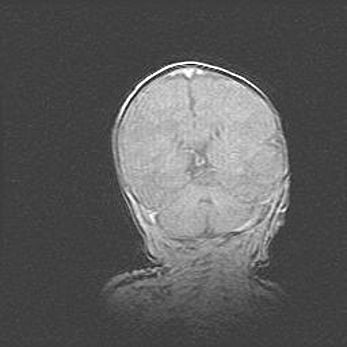

Открытая гидроцефалия.

Возраст: 9 месяцев 12 дней

Вес: 6800 г

Пол: мужской

Окружность головы: 41,5 см

Срок гестации: 28 недель

Гидроцефалия головного мозга у новорожденных имеет характерный признак: опережающий рост окружности головы приводит к визуально хорошо определяемой гидроцефальной форме сильно увеличенного в объёме черепа. Детские неврологи определяют следующие симптомы гидроцефалии у грудничков: выбухающий напряжённый родничок, частое запрокидывание головы, смещение глазных яблок к низу.